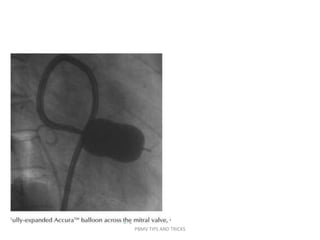

• After the balloon catheter is across the mitral orifice,

the distal portion of the balloon is inflated more fully

and the catheter is pulled back gently to confirm that

the inflated distal portion of the balloon is secure

across the valve.

• As further volume is added to the balloon, the

proximal end inflates to lock the valve between the

proximal and distal balloon.

• Inflation to precalibrated volume then dilates the

valve orifice to the corresponding preset size